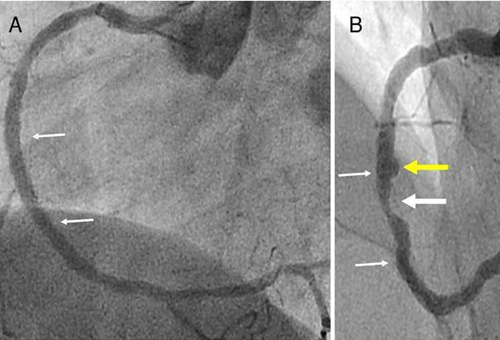

目前檢測冠心病有兩種手段,一是冠脈CT檢查,二是冠脈造影檢查。

冠脈CT是在患者手臂靜脈輸入對比造影劑,然后再進行心臟掃描,檢查可能存在的冠狀動脈病變。目前,雖不推薦將冠脈CT作為查體必備項目,但對于有患冠心病的高危人群,這項檢查是非常適合的,它無創(chuàng)準確,方便快捷,用于冠心病的初步篩查和冠脈血管評估。

對于這兩個檢查,很多病人會問:“這兩個檢查到底有什么區(qū)別?”其實冠脈CT就像平時輸液一樣在患者手臂的靜脈里輸入對比造影劑,然后對心臟進行掃描,借以尋找可能存在的冠狀動脈病變。快捷方便,準確性也高,患者接受起來比較容易。而冠脈造影屬于有創(chuàng)檢查且需住院,穿刺時還要局麻。但冠脈造影不僅可以明確診斷有無冠心病,而且可了解病變的部位、范圍及嚴重程度,還可同時進行支架介入治療,是冠脈CT檢查無法取代的。但不是所有的患者都適合做冠脈造影,嚴格聽從醫(yī)生的建議很重要。